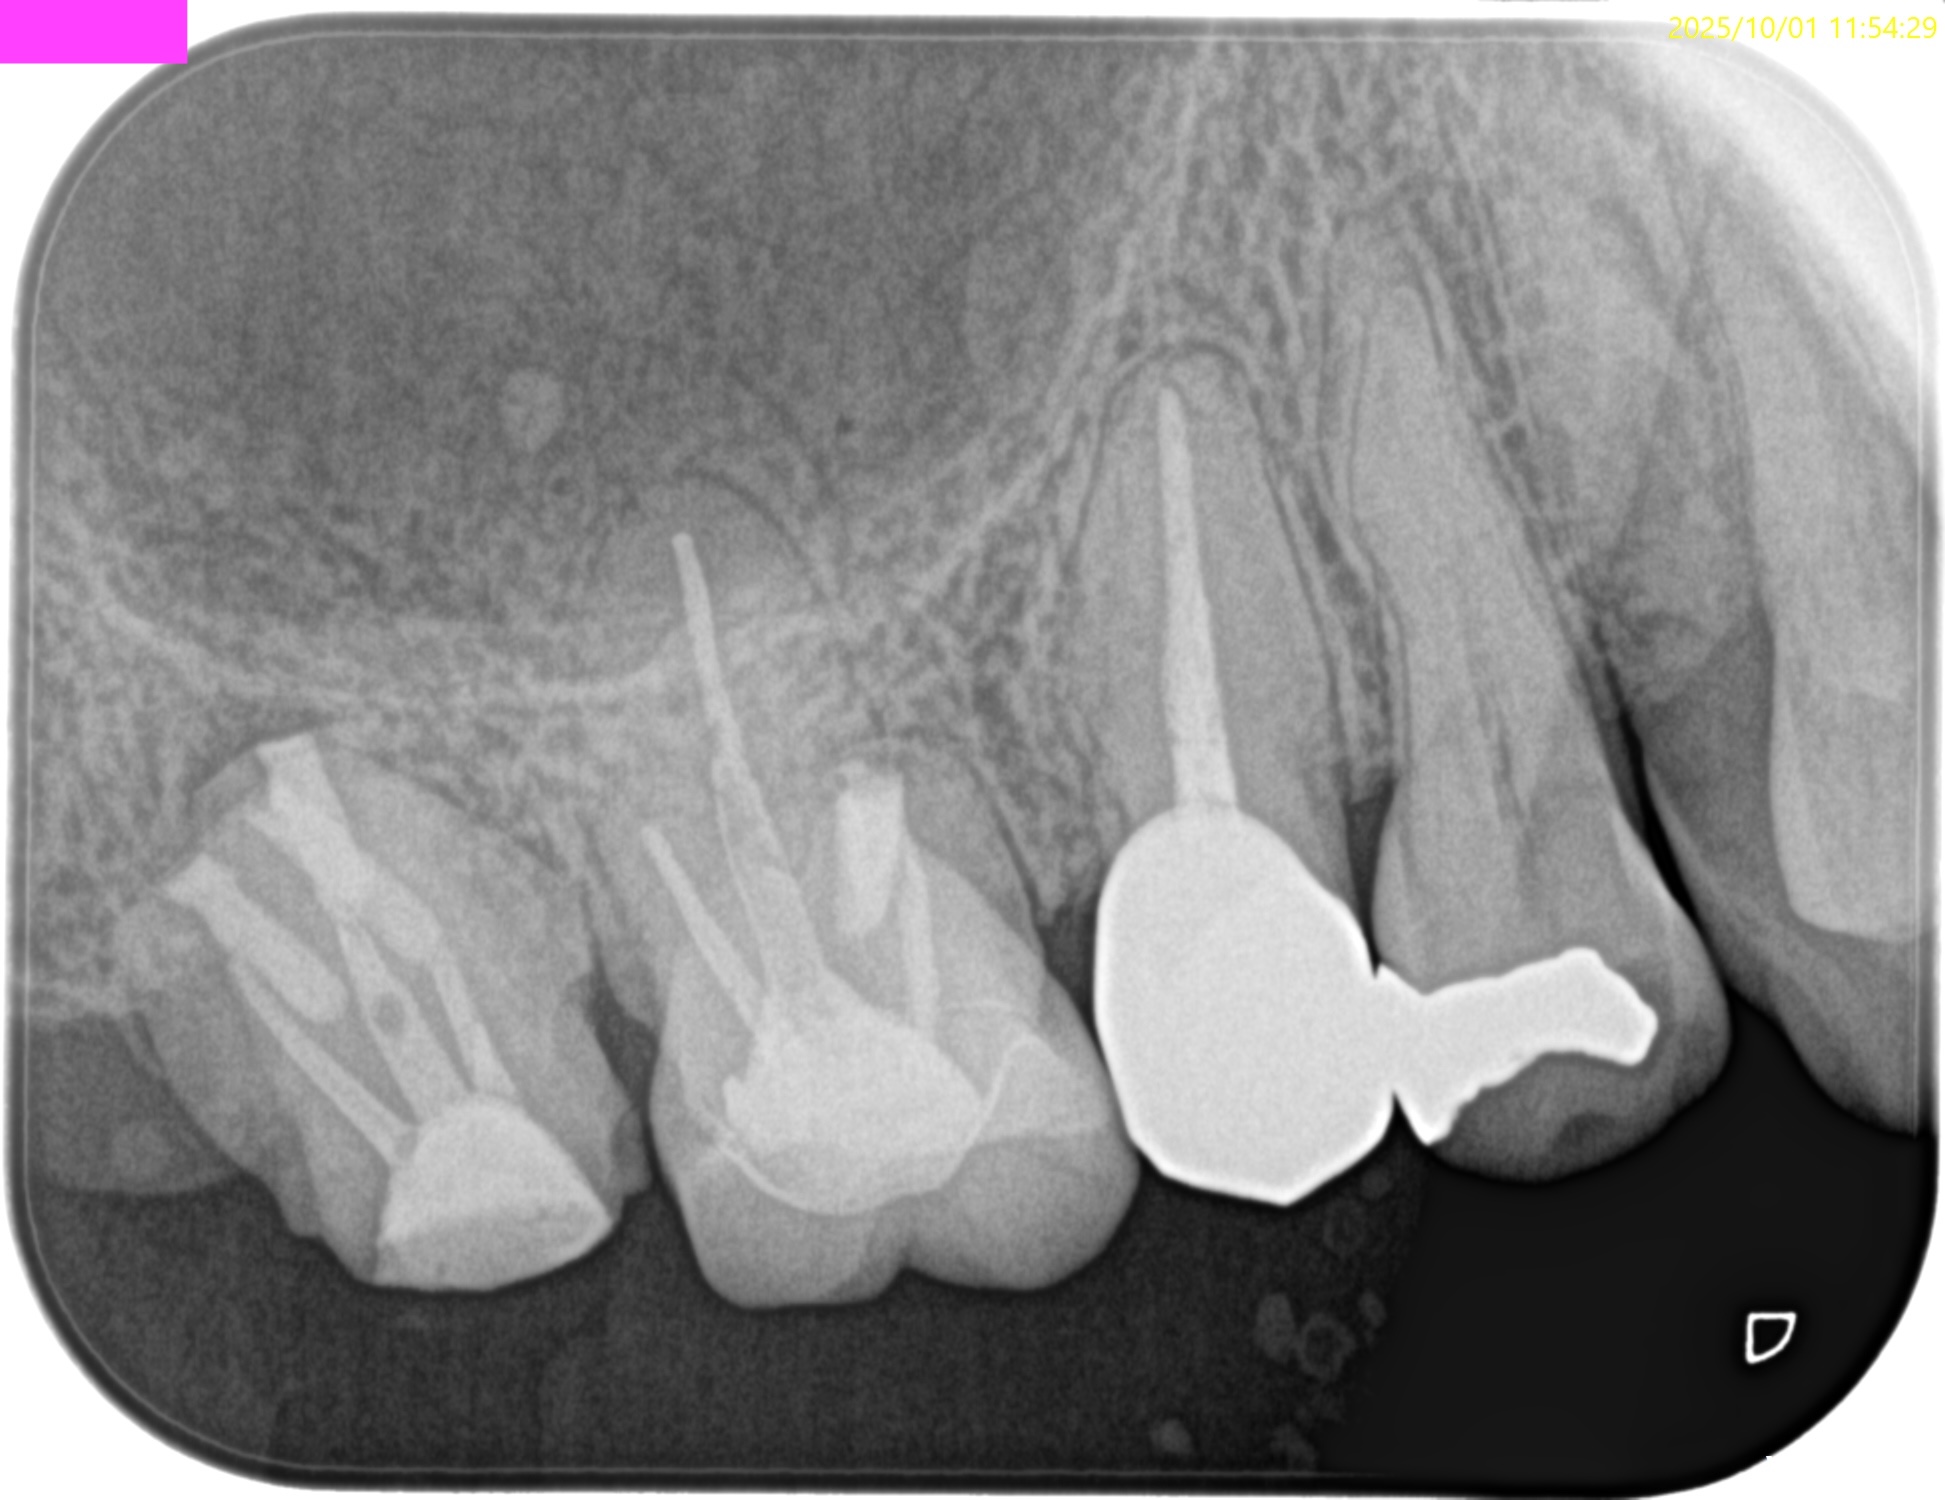

#2 Intentional Replantation 2M recall(2025.10.1)

MB

DB

P